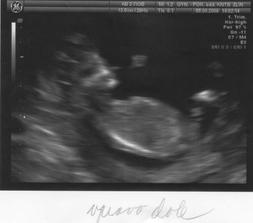

25.6. na utz dva váčky, zatím 1 srdíčko.

3.7. už nám tlučou 2 srdíčka. Je to moc krásný pocit. 🙂) Na OBI, jsem se rozloučila a byla odeslána ke svému gynekologovi. Ještě mě tam, ale čeká jedna kontrola v rizikové poradně pro vícečetné těhu, kterou mi pan docent nabídnul. Jsem ráda, že mají ještě zájem mě na Obi vidět. Jsou tam všichni moc hodní, jak sestřičky tak doktoři, opravdu jsem byla s jejich přístupem mooc spokojená.